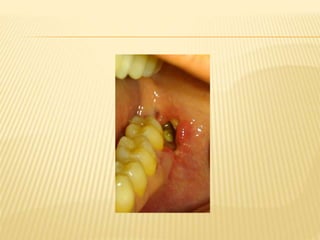

 A sclerosed bordercalled an involucrum forms around the affected area. The involucrum prevents blood supply from reaching the affected part. This results in the formation of pieces of sequestra or necrotic bone surrounded by pus. A fistulous tract may develop by the suppuration perforating the cortical bone and periosteum. The fistulous tract discharges pus onto the overlying skin or mucosa.

 FibrinolyticAlveolitis (DrySocket)  This postoperative complication appears 2–3 days after the extraction. During this period, the blood clot disintegrates and is dislodged, resulting in delayed healing and necrosis of the bone surface of the socket. This disturbance is termed fibrinolytic alveolitis and is characterized by an empty socket, fetid breath odor, a bad taste in the mouth, denuded bone walls, and severe pain that radiates to other areas of the head.  As for the etiology and pathogenesis of dry socket, various factors have been cited, some of which include dense and sclerotic bone surrounding the tooth, infection during or after the extraction, injury of the alveolus, and infiltration anesthesia.